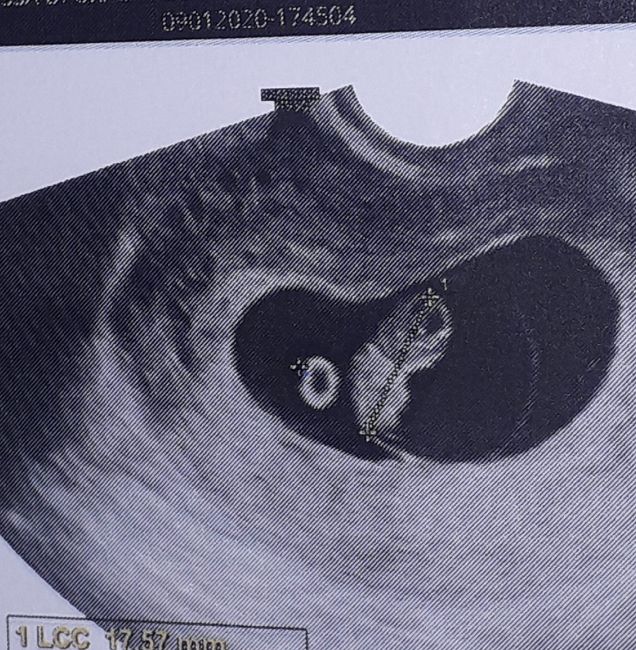

Prima ecografia

È andata benissimo e ho pianto di gioia sono un po indietro a 6+5 questa volta finalmente c'è un embrioncino di 7,1mm con un cuore che batteva forte forte. Emozioni uniche❤️

Ciao Annalisa, io ho fatto la prima eco alle tue settimane.

Fagiolino di 1.2 cm, cuoricino che batteva forte!

Prima ecografia 1